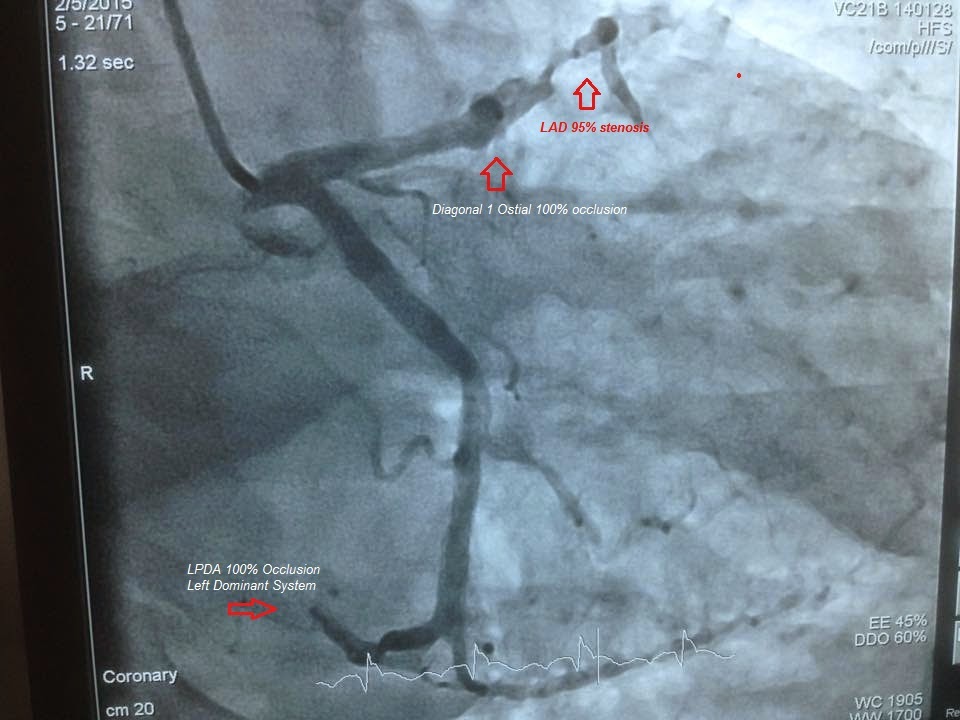

#7- Angiography shows Small Non-dominant RCA ! and it is 100% CTO, so when there is non-dominant it has no value ! and we see Left posterior descending artery arising from LCx showing left dominant then LPDA is also 100% acutely occluded , and LAD Mid is 95% occluded and D1 is 100% ostial occlusion !

#8- Result- Echo+ECG shown Anterior and Posterior wall MI . Angiography did show that this patient have acute Posterior and Anterior wall simultaneously but this True posterior is the result of LPDA not RCA , and anterior is due to LAD and D1.